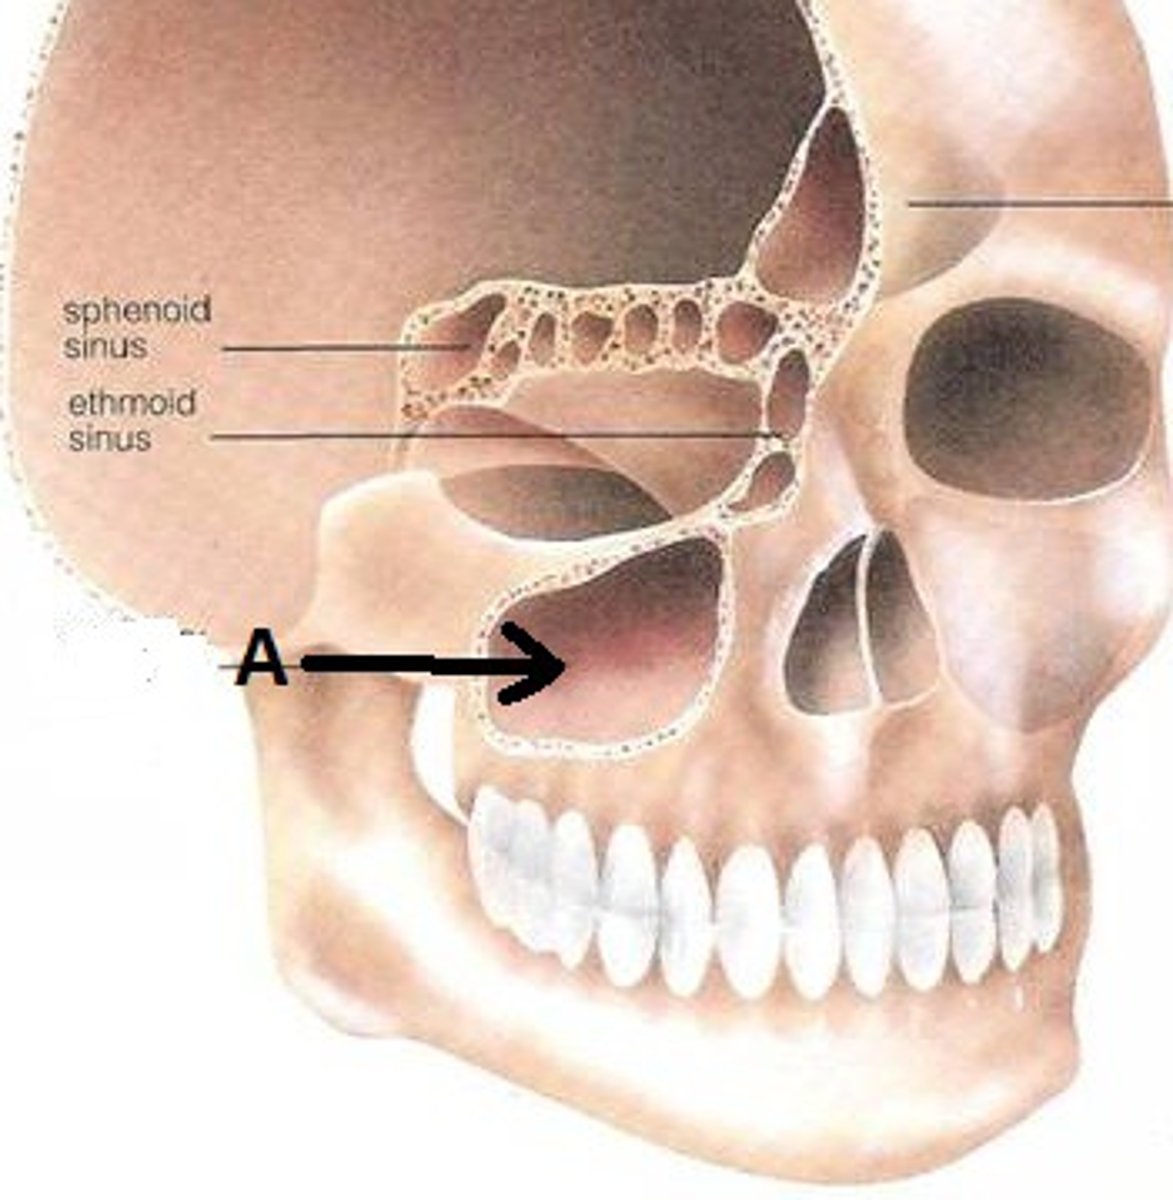

maxillary sinus

sinus on either side of the nasal cavity below the eyes

sphenoid sinus

sinus that sits just UNDER the sella turcica. It is posterior to the nose, and slightly superior

ethmoid sinus

Nasal Sinus located between the nose and the orbits.